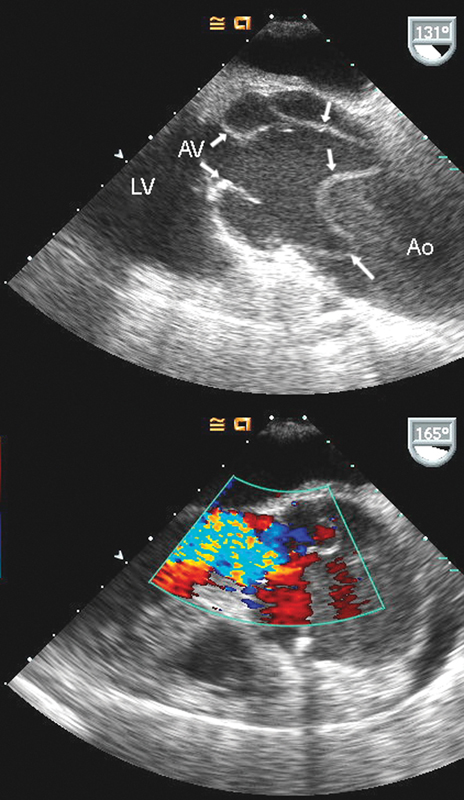

فحوصات تشخيصية لبعض امراض القلب والشرايين التاجية